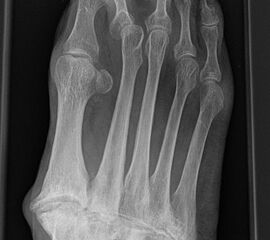

Die Überbelastung des Metatarsale II und III im distalen Bereich äußert sich in Druckschmerzen und Schwielenbildung plantar unter den Metatarsale II und III Köpfen (Abb. 1). Auch degenerative Veränderungen der plantaren Kapsel und der plantaren Platte der Metatarsophalangealgelenke treten auf, was zu einer Insuffizienz der Grundgelenke mit Subluxation oder Luxation der Kleinzehen führt (Abb. 2 und 3).

Die Überbelastung im Schaftbereich wird selten von den Patienten wahrgenommen. Manchmal findet sich vor allem am Os metatarsale II proximal eine Stressfraktur. Adaptiert sich der Knochen, kann im Röntgenbild häufig eine Kortikalisverdickung im Bereich der Metatarsale II und III Schäfte als Ausdruck einer vermehrten Lasteinleitung beobachtet werden (Abb. 4).